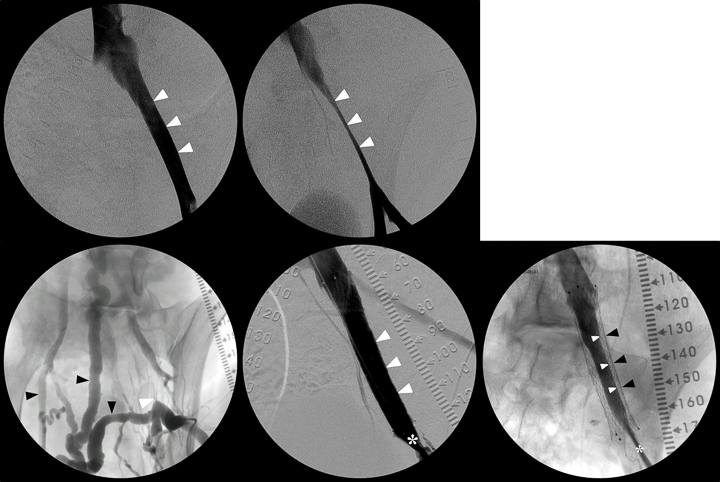

My Junior Faculty Develpment Program (JFDP) project is a translational research effort aiming to address critical gaps in venous thromboembolism (VTE) by analyzing subacute/chronic venous clots and optimizing existing animal models to better replicate human disease.